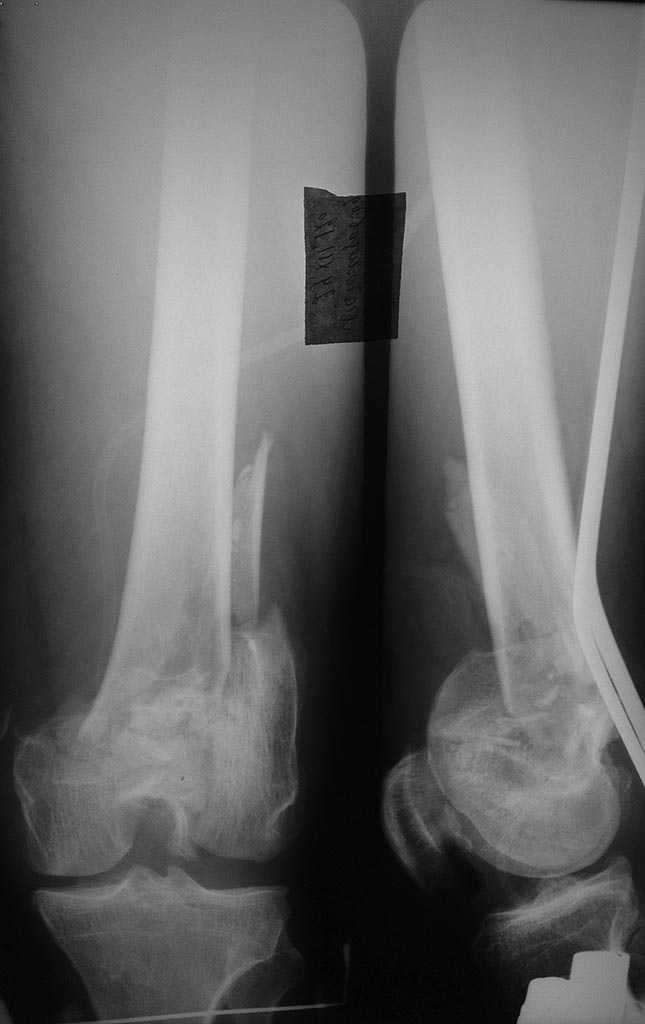

Помогите определиться с тактикой и объемом оперативного вмешательства,пациент мужчина 55

лет травма получена в ДТП 21.12.12г